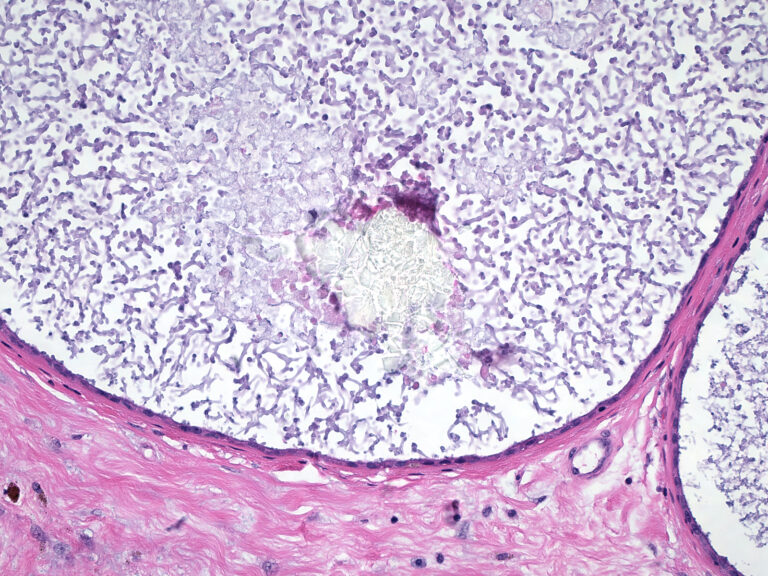

Cancer cells depend on free iron to multiply. Free iron is needed for DNA replication in rapidly dividing cells. Several studies, (but not all) have shown that free iron concentrations in ductal breast tissue has a major role in cancer development and progression to aggressive / deadly cancers. Wu T et al, 2004; Cade J et al, 1998; Kalinowski DS, Richardson DR, 2005

Free iron levels in breast ductal tissue can become dangerously high over time inducing malignant tumor formation.

Breast cancer nipple fluid found to have ~2X aluminum and 5X ferritin levels than normal. Department of Biomolecular Sciences, Urbino Italy found that in addition to almost twice as much aluminum, that women with breast cancer had 5X higher levels of ferritin, an iron transport protein (also confirmed in other studies).

- Ductal nipple fluid. Extracted via a breast pump in pre- and post-menopausal women is examined to measure levels of such as iron, ferritin (an iron-binding protein), CRP (a measure of breast inflammation) and aluminum. Mannello F, et al, 2011; Shpyleva SI et al, 2011